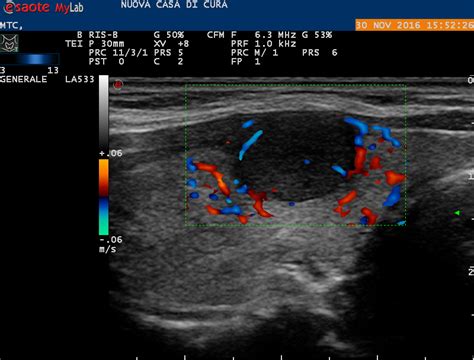

Ecografia Tiroidea

L'ecografia tiroidea con color doppler è l'esame di elezione per la diagnosi e la caratterizzazione dei noduli tiroidei. Questa metodica non invasiva permette di determinare la presenza, le dimensioni, la forma, la struttura interna (solida, cistica, mista) e le caratteristiche ecografiche dei noduli, fornendo una stima del rischio di malignità. L'ecografia è anche essenziale per guidare l'ago durante la biopsia.